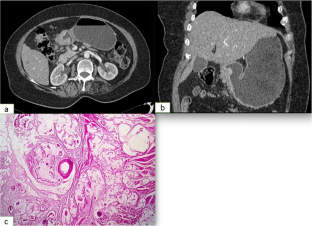

Fig. 1